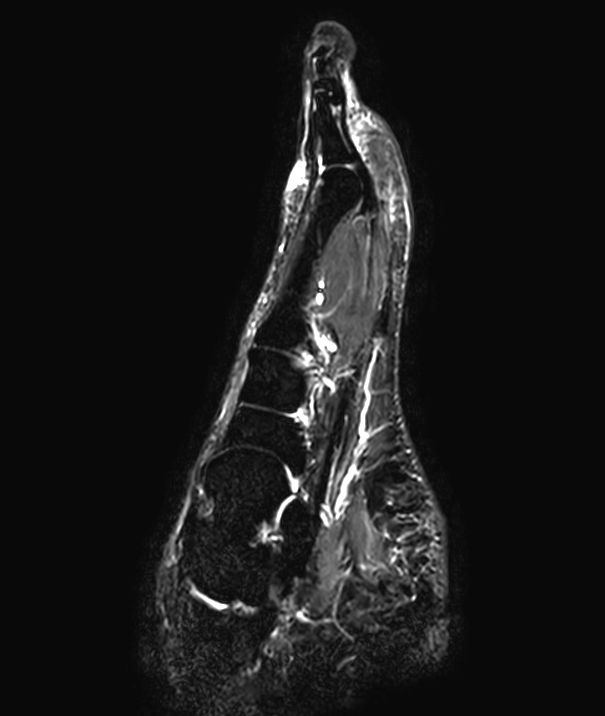

Sagittal STIR TSE